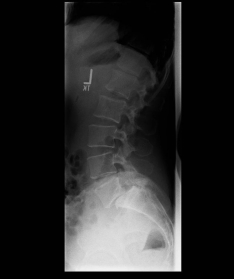

Spondylolisthese ISpondylolisthese II

X-ray image of a slipped vertebra in the lower lumbar spine before and after surgery